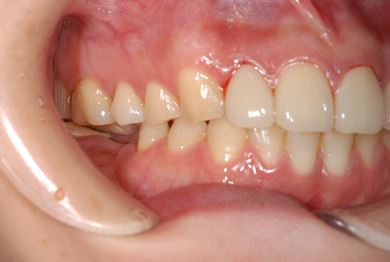

治療前

• 治療前